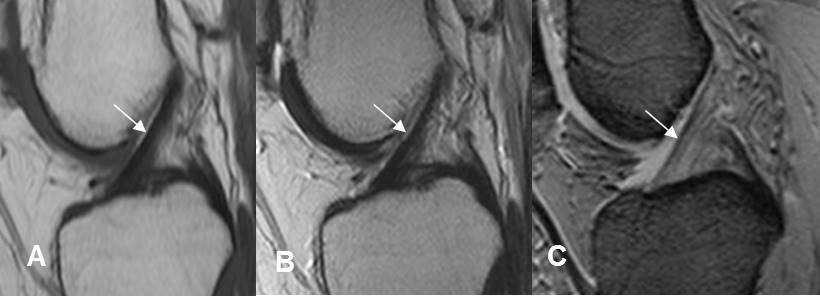

La RM es la modalidad de elección para el estudio del sistema osteomuscular. (1). Es muy sensible para la valoración del trauma con Rx y TAC normales y permite detectar contusiones de la microtrabécula, fracturas intraóseas y fracturas osteocondrales. (1). (Fig 23 A, B y C).

En casos de fracturas se encuentran imágenes lineales hipointensas en T1, en el interior de la zona de edema trabecular. (1). La RM es la primera línea para el diagnóstico de fracturas ocultas de la cabeza femoral y el escafoides. (1). (Fig 24 y 25).

Fig 23 A. Fractura oculta.

A: Rx AP. Cambios degenerativos en la sínfisis púbica, pero sin detectar fracturas.

B: RM axial en T1 y C: RM axial en STIR. Fractura no desplazada del ramo isquiopúbico (Flechas), con cambios inflamatorios en los tejidos blandos.

Fig 23 B. Trauma oculto.

A: Rx AP y B: Rx lateral. Paciente con trauma directo, donde no se encuentran alteraciones.

C: RM coronal en T1 y D: RM sagital en T1. Edema óseo del platillo tibial lateral, con fisura no deprimida.

Fig 23 C. Lesión condral.

A: Rx AP. No se encuentran alteraciones.

B: RM sagital en T2 y C: RM sagital en STIR. Defecto en el cartílago sobre el borde inferior del cóndilo femoral medial, por desprendimiento condral.